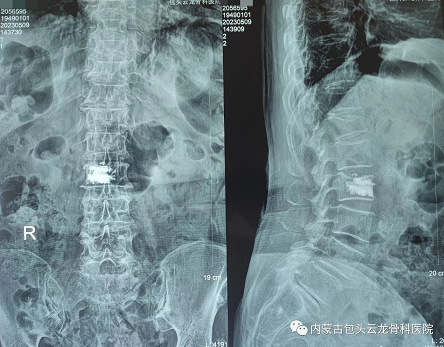

▲图为患者术后影像

通过手术过程中正侧位进行伤椎识别,得到患者伤椎的姿态以及实际的穿刺角度,之后机械臂根据软件参数进行“亚毫米级”精准定位,配合医生完成手术。